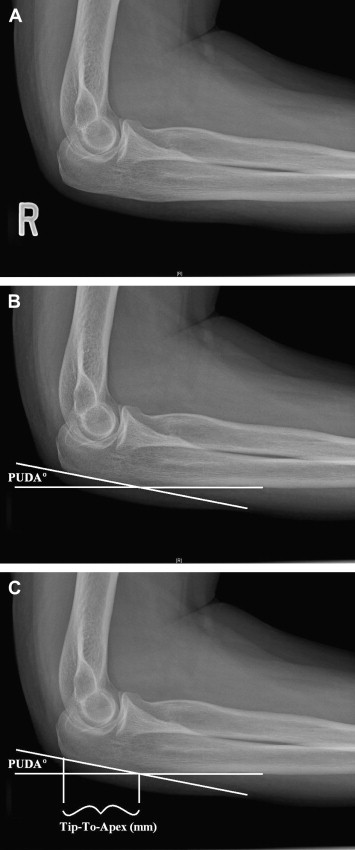

What is the PUDA angle?

[JAAOS 2013;21:149-160]

A

PUDA = proximal ulna dorsal angulation

• The average PUDA is 6° measured 5cm distal to the tip of the olecranon

• Increased PUDA associated with decreased terminal elbow extension